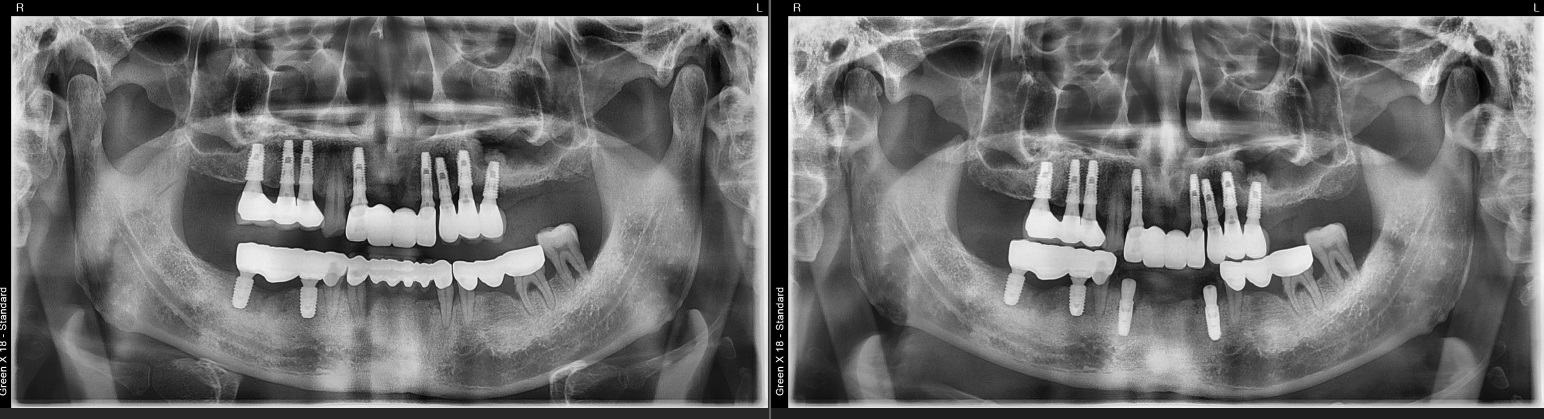

전악 임플란트가

한시간만에?

안면 골격을 다루는

구강악안면외과 전문의 경험으로

짧은 시간에도 정밀한 식립을 완성합니다.

임플란트의 5년 성공율은

최근 발표된 논문들까지 종합해도

90~95% 이상으로 발표되고 있습니다.

매우 높은 성공율입니다.

하지만, 실패한 임플란트를 같은 자리에

재식립했을 때의 성공률은 70%대로 떨어집니다.

(J Oral Maxillofac Surg 78:375-385, 2020)

초기에 발견하고 재식립했을 때는 성공율이 높아집니다.